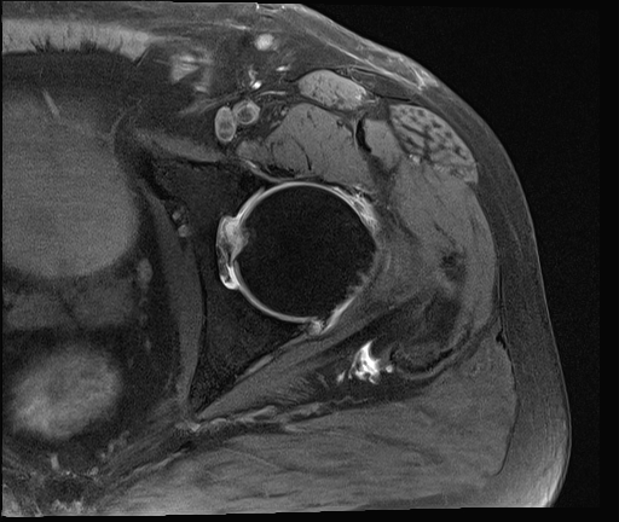

Diagnostic Testing. The evaluating clinicians obtained AP (Figure 1) and lateral (Figure 2) radiographs as well as magnetic resonance arthrogram (MRA) images of the left hip (Figures 3 and 4).

Figure 4. Axial T2 MRI of the hip with arthrogram is shown.